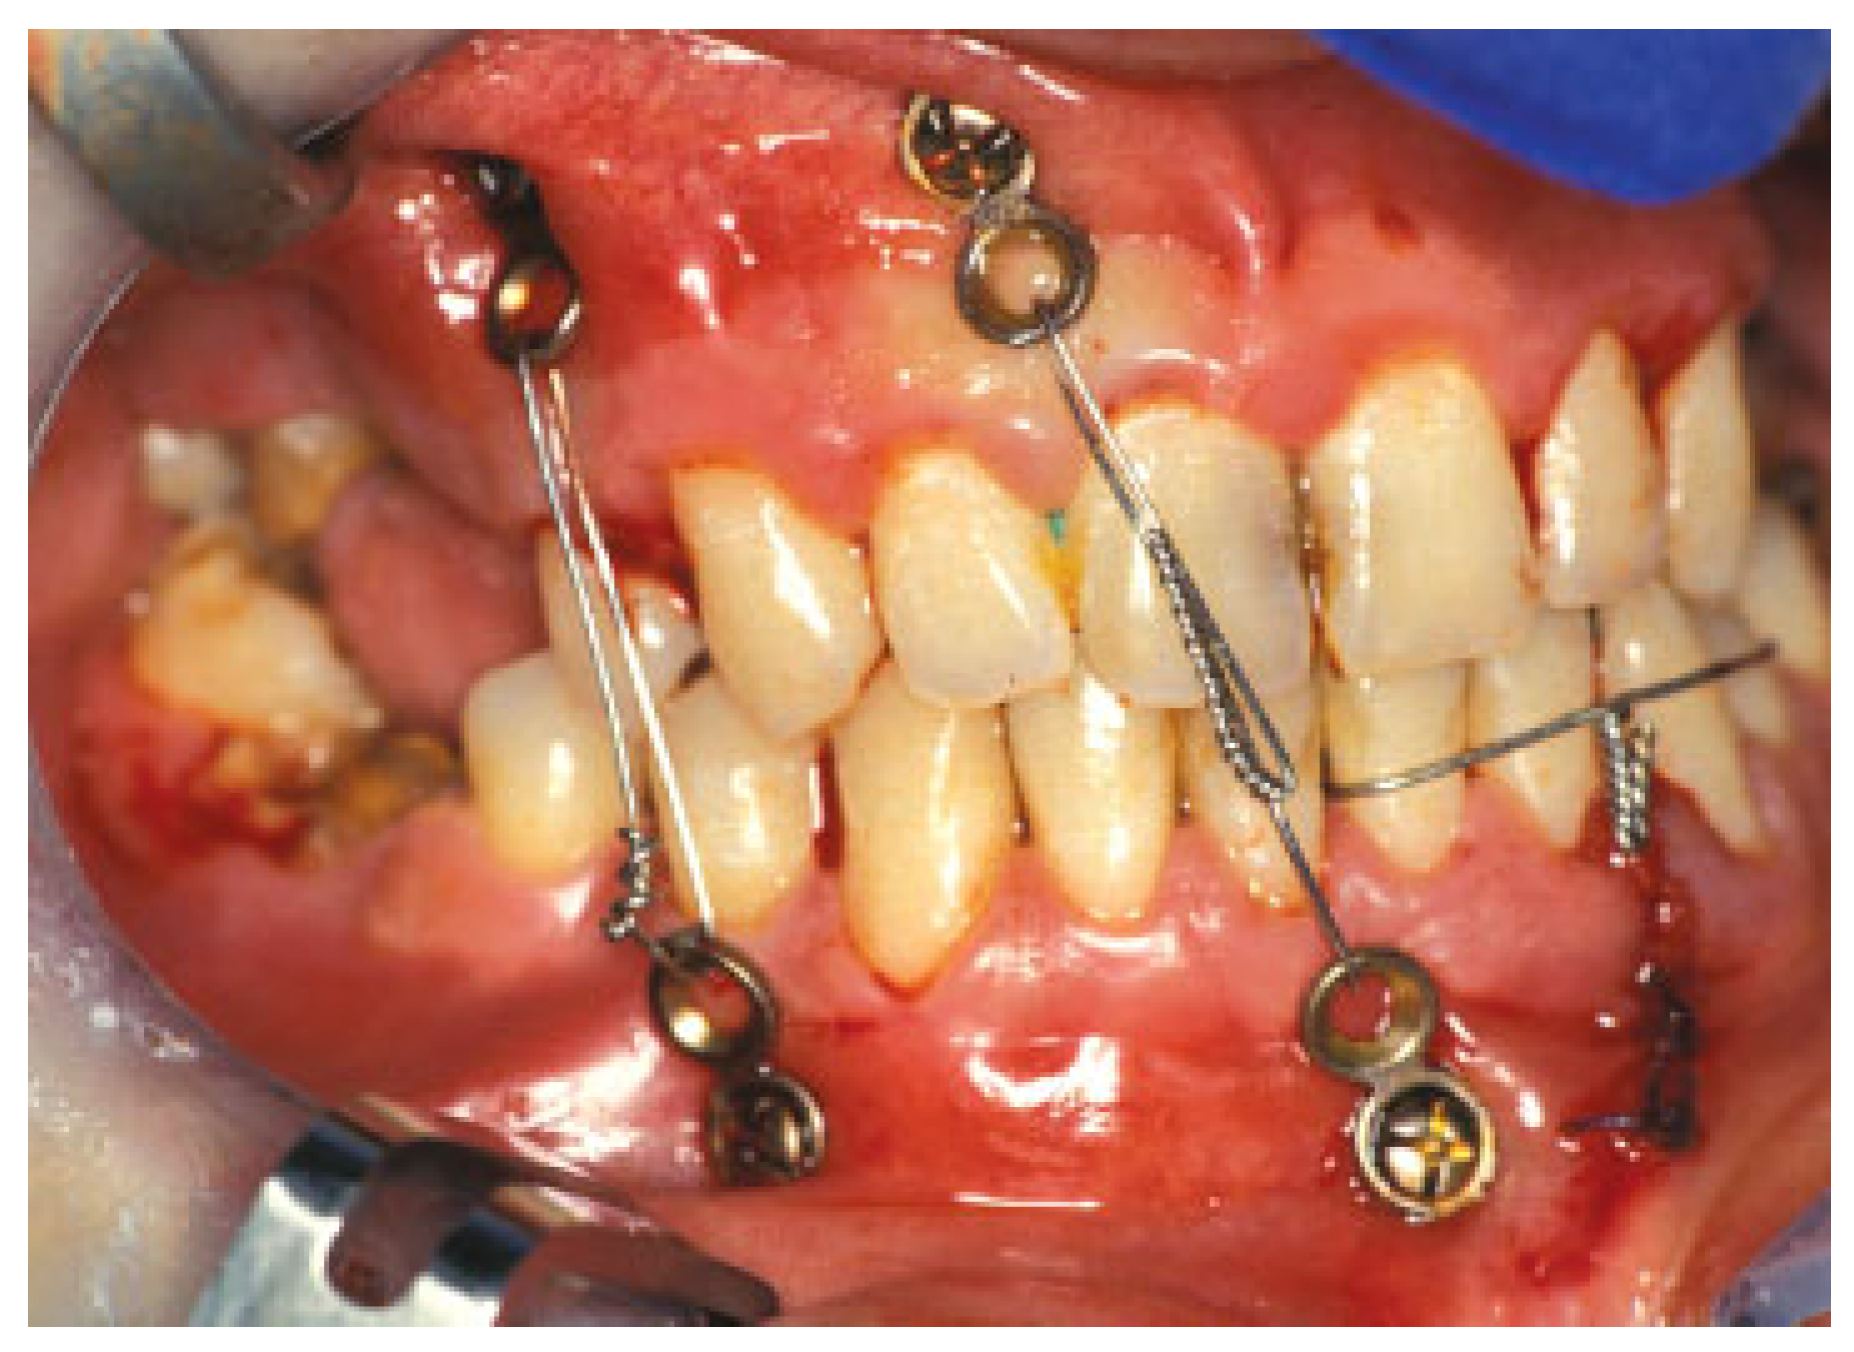

The increasingly popular usage of conventional bone screws with the heads kept at 4 to 5 mm above the mucosa or bone level paved the way for the commercial manufacturing of explicitly designed self-tapping or self-drilling MMF screws during recent years. Among the forerunners of mere single piece MMF screws were screws used in conjunction with stainless steel wire hooks or short, two or three hole, segments of miniplates (“hanger plates”). The coupled hooks or the empty plate holes served as anchors for MMF ligatures (Figure 1). An example still of interest is the spino-mental fixation, where two screws fitted with hooks are positioned below the anterior nasal spine and shortly above the mental protuberance to establish MMF in a very simple manner [8,9].

Figure 1. “Hanger plates” for mandibulo-maxillary fixation (MMF). Short plate segments fixed transmucously with cortical bone screws are used as fasteners for the intermaxillary wire ligatures. “Hanger plates” were among the forerunners of specialized MMF screws.